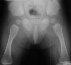

RADIOGRAPHS:

Plain x-ray's showed a sixth metacarpal and phalanx on the ulnar border

of both hands

.

The distal phalanges are shortened relative to the proximal and distal

segments. The pelvis

has

small, squared iliac crests with spikes of bone at the triradiate cartilages.

The tibial segments

are

disproportionately shorter than the femoral segments.

- Characteristic features of the pelvis includes:

- small iliac crests and sciatic notches

- originating from the triradiate cartilage a distally directed spike

of bone

- The proximal tibial epiphysis has a growth failure which results in

a valgus deformity of the knee

- The fibula is disproportionately shorter than the tibia